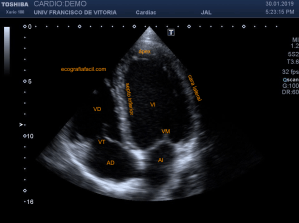

142. Ecocardiografía.Plano Apical 4 cámaras